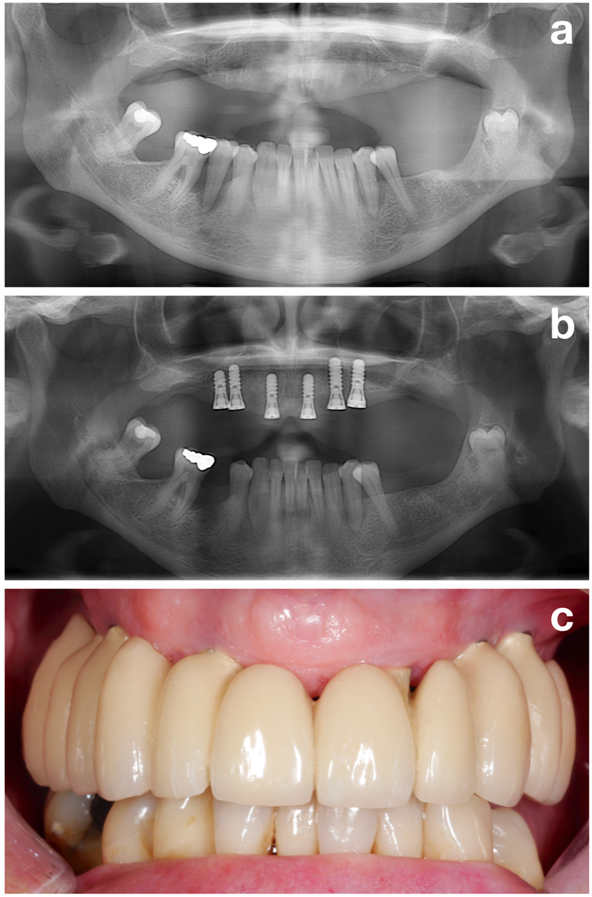

Das NIWOP-Konzept (Abbildung 1) besteht aus drei wesentlichen Phasen: (1) Vorbehandlung, (2) Implantation und (3) Recallprogramm bzw. unterstützende Therapie.

Im ersten Teil (also in der Vorbehandlungsphase) werden alle potenziellen Risikofaktoren ermittelt, um den Patienten bestmöglich auf die spätere Implantation vorzubereiten. Der Fokus liegt dabei jedoch auf einem der wichtigsten Aspekte, nämlich dem Schaffen eines stabilen parodontalen Zustandes (Abbildung 2).

Abschließend lässt sich festhalten, dass ein stabiler parodontaler Zustand neben anderen Zielen wie der Raucherentwöhnung oder einer einwandfreien Mundhygiene (Abbildung 3) einer der wichtigsten Aspekte im Rahmen der Vorbehandlungsphase darstellt. Dieser Zustand sollte vor der Implantation erreicht werden.